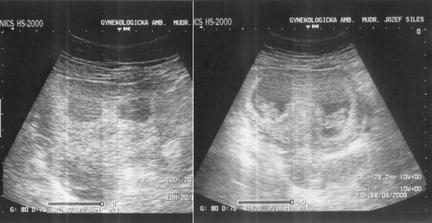

Naše twins 🙂 výbavička